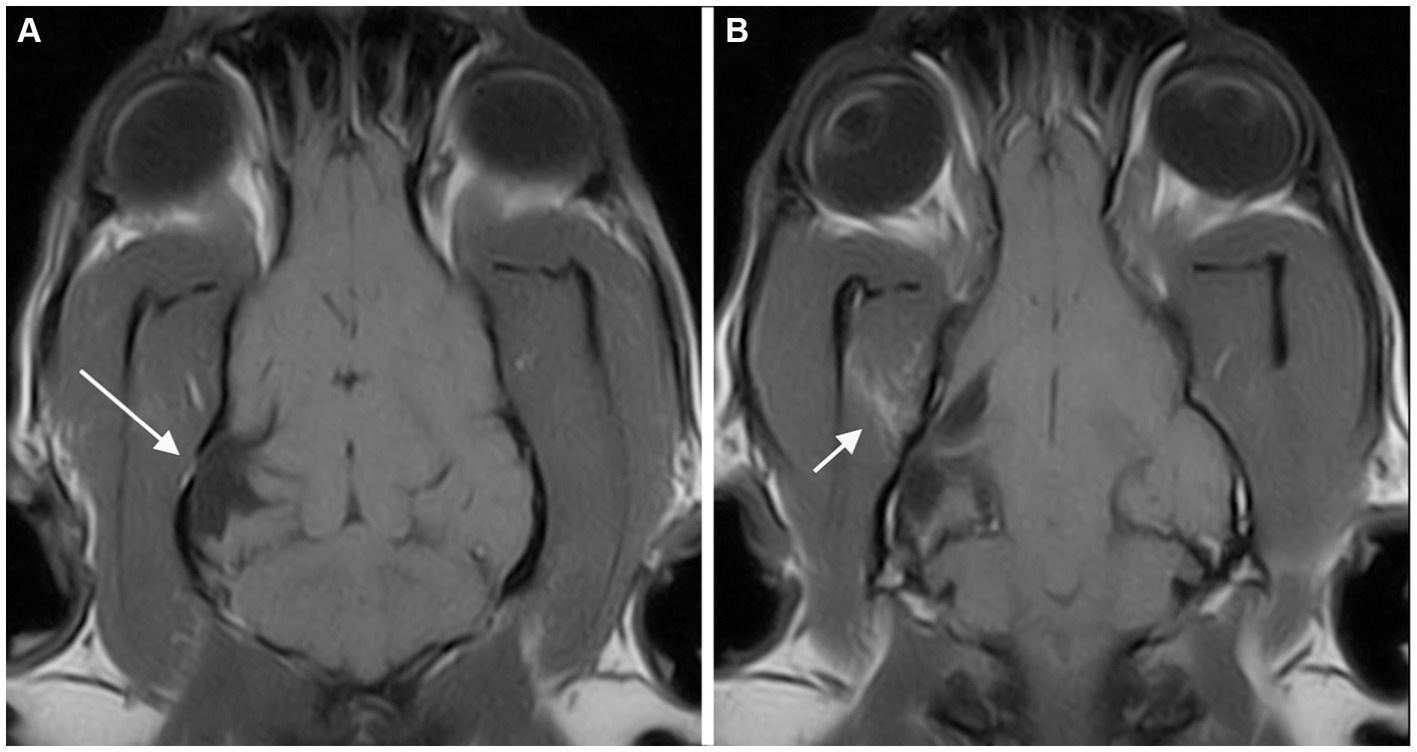

Figure 1

Dorsal T1-weighted (A) and transverse 3D-Gradient Echo in Steady State at the level of the thalamus (B) MR-images of the brain of a cat revealed two CSF-filled cavities consistent with bilateral porencephaly. A focal lesion located in the right parietal lobe (long arrow) showed communication with neither the ipsilateral lateral ventricle nor the sub-arachnoid space. A second, extensive lesion extending from the left lateral ventricle to the cortical surface at the level of the parietal and temporal lobes (short arrow) is seen.

Twenty-one of 32 patients were examined with a low-field MR scanner and 11/32 with a high-field MR scanner. At least a T2 weighted (T2W) or a T1 weighted (T1W) spin echo (SE) sequence was available in all spatial planes for each MRI study. T1W SE sequences after intravenous administration of 0.2 mL/kg of gadoteric acid were available in all cases. Fluid-Attenuated Inversion Recovery (FLAIR) sequences were available in 27/32 cases. The MRI features of the PCs and musculoskeletal changes are presented in Table 3. A total of thirty-nine PCs were seen. All cases showed either one or two PCs. A single PC was found in 25 (78.1%) cases. In this group, a clear communication with both the ventricular system and the subarachnoid space was seen in 16/25 cases and with the subarachnoid space alone or the ventricular system alone in 7/25 and 2/25 cases, respectively. Two PCs were found in 7 (21.9%) cases (Figure 1), of which both lesions showed a communication with both the ventricular system and the subarachnoid space in four of seven cases. In each of the remaining 3/7 cases, there was a lesion communicating with both the CSF spaces and the other lesion communicating with the subarachnoid space alone (1 case), the ventricular system alone (1 case), or showing no communication at all (1 case). The PCs were confined in a single lobe (6/39) or involved multiple lobes (33/39). The most affected cerebral lobe was the parietal lobe (n = 20), and the least affected was the olfactory lobe (n = 10). The defects involved both the GM and WM in 25/32 cases (78.1%). Contrast enhancement was absent in 27/32 cases and present in 5/32 cases.